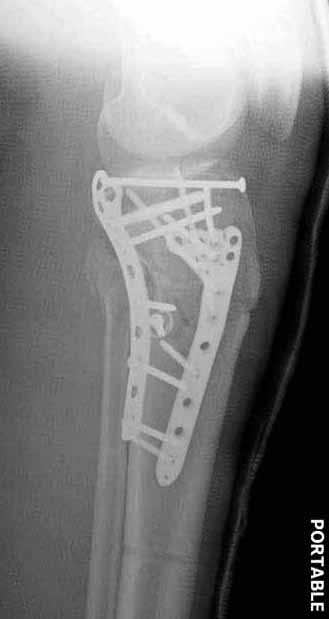

Двухколоннный перелом тибиал плато с вовлечением проксимального диафиза. Внутрисуставной компонент без смещения, и такой перелом можно лечить любым из описанных методов, о которых говорят наши коллеги.

Удобно аппаратом Илизарова или интрамедуллярным гвоздем. Гвозди не так сложно, как пугают, тем более Александр готов помощь с методичкой. Сперва надо установить компрессирующие шурупы на мыщелки. Давно отказались в пользу 3.5-4.0 мм кортикальных вместо толстых спонгиозных, потому что не доказаны преимущества толстых шурупов. Тонкие шурупы в субхондральной зоне смотрятся намного элегантнее, чем толстые 6.5.

Это мероприятие превращает перелом в простой диафизарный, который легко можно фиксировать гвоздем. Шурупы надо установить сзади предполагаемого места введения гвоздя.

Для изолированных переломов медиального тибиал плато, фиксацию можно провести “медиальной пластиной”. Некоторые компании, например Smith & Nephew делают медиальные и медиально-задние пластины, но они мягкие, и легко можно создать нужный контур. Жесткость создается за счет фиксации жесткими пластинами, например экстра артикулярной пластиной для дистального плеча от Synthes. Медиальный доступ тоже не из легких, надо работать между pes and medial gastroc.

Частая ошибка, когда фиксацию двух колонного перелома проводят одиночной пластиной, т.е с одной стороны, и такая фиксация не удерживает, происходит вторичноое смещение. Необходимо нейтрализовать второй пластиной или дополнительным наружным фиксатором.

Если у вас, кроме пластины, нет другого альтернативного варианта, тогда, учитывая мягкотканые проблемы с наружной стороны, я бы рекомендовал операцию делать в два этапа. Преимущества, сперва репозиция и фиксация перелома с медиальной стороны, а затем, после улучшения состояния мягких тканей, зафиксировать с латеральной стороны. Современные пластины имеют латеральный Jig для перкутанных мини доступов.

В приложении этапы фиксации Both Column Fx и пластиной Synthes для плеча при переломе медиального мыщелка.